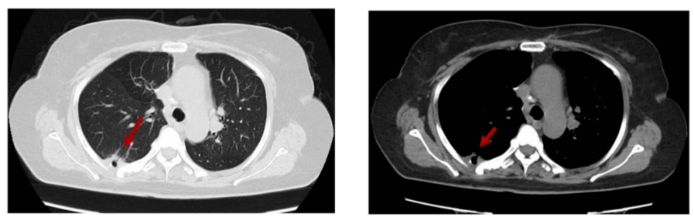

2022-7-23 随访复查胸腹CT平扫示右下肺胸膜下小片实变影伴空洞,较前片变化不大。评效SD。

图6 2022-7末次随访:右下肺胸膜下小片实变影伴空洞